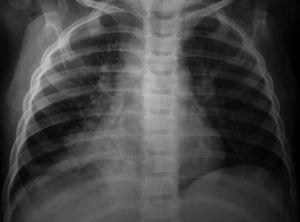

A los niños con Mantoux positivo se les realizó una radiografía de tórax que fue patológica en 10 de los 11 (90,9 %) que fueron derivados a nuestro hospital. El niño sin alteraciones radiológicas recibió profilaxis con isoniazida durante 9 meses. La edad media fue de 23,1 meses (11-42 meses). De estos 10 niños, siete estaban sintomáticos en el momento del estudio, cinco presentaban tos, cinco fiebre y uno eritema nudoso (tabla 1). Las imágenes radiológicas mostraron condensación parenquimatosa en el 90 % de los pacientes y adenopatía parahiliar en el 50 % (figs. 1-3).

Figura 3. Paciente n.º 1 (inicial). Condensación del lóbulo medio derecho.

Los 10 pacientes con radiografía patológica iniciaron el tratamiento con isoniazida, rifampicina y pirazinamida. Siete pacientes presentaron una buena evolución no precisando otros tratamientos ni exámenes complementarios. Sin embargo, en 3 niños se observaron alteraciones de la ventilación en la radiografía de tórax en forma de atelectasia al inicio del tratamiento. En estos niños se practicó una broncoscopia y se añadieron corticoides al tratamiento tuberculostático. Los 3 niños tuvieron buena evolución. Al finalizar el tratamiento de 6 meses, todos los niños estaban asintomáticos y con normalización de las imágenes radiológicas. La estancia media en el hospital fue de 5 días. No se detectaron casos de tuberculosis en los miembros de la familia de los niños enfermos.

En pacientes pediátricos, la presencia de linfadenopatía hiliar, mediastínica o cervical, afección pulmonar con infiltrados segmentarios o lobulares, neumonía consolidada, atelectasias, derrame pleural o tuberculosis miliar representan el espectro de enfermedad en este grupo de población 32. En nuestros casos la forma de presentación más frecuente fue la consolidación pulmonar seguida de adenopatías hiliares y atelectasia pulmonar.

Las lesiones pulmonares tuberculosas se encuentran con mayor frecuencia en el pulmón derecho (55 %). En nuestro estudio, de los niños que presentaban imágenes de condensación parenquimatosa, cuatro se localizaron en el pulmón derecho y cinco en el izquierdo. De preferencia las lesiones se localizan en las porciones mejor ventiladas, parte baja del lóbulo pulmonar superior y alta del inferior. Muy raras veces en el vértice. En la mayoría de los casos, el foco es único, raras veces doble 33.